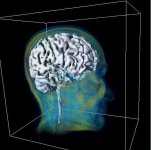

Ein besonders aktueller Schwerpunkt des Welfenlab ist die Visualisierung von Voxeldaten aus dem Bereich der Medizin. Unter einem Voxel kann man sich das dreidimensionale Gegenstück eines Pixels vorstellen. Während ein Pixel (bestehend aus einer x und y Koordinate zusammen mit einem Farbwert) einen Punkt auf einem Computermonitor beschreibt, besitzt ein Voxel zusätzlich eine z-Koordinate. Solche Voxeldaten werden u.a. durch verschiedene bildgebende Verfahren der Medizin gewonnen, z.B. durch Computertomographie (CT) oder Magnetresonanztomographie (MRT). Aus Sicht der Informatik stellt sich die Frage, wie solche Voxeldaten in einer für den Menschen verständlichen Art und Weise dargestellt werden können. Je nach Anwendung kommt es dabei entweder darauf an eine besonders schöne und leicht verständliche Visualisierung zu finden, oder eine möglichst schnelle, interaktive Darstellung bei der sich der Betrachter um das virtuelle Objekt herum oder sogar hindurch bewegen kann.

Zusammen mit dem Problem der Visualisierung tritt oft auch das Problem der Segmentierung auf. Unter diesem Begriff versteht man die Erzeugung von inhaltlich zusammenhängenden Regionen durch das Zusammenfassen von Pixeln oder Voxeln entsprechend einem bestimmten Homogenitätskriterium. Ein CT-Voxeldatensatz kann z.B. eine Aufnahme eines menschlichen Kopfes darstellen. Ein Teil dieser Aufnahme besteht aus Knochen, ein Teil des Knochens würde von einem Mediziner als "Unterkiefer" bezeichnet. Beides, sowohl "Knochen" als Oberbegriff als auch "Unterkiefer" als Teilmenge von "Knochen", bezeichnet man als Segment und die (manuelle oder automatische) Erzeugung eines solchen Segments als Segmentierung.